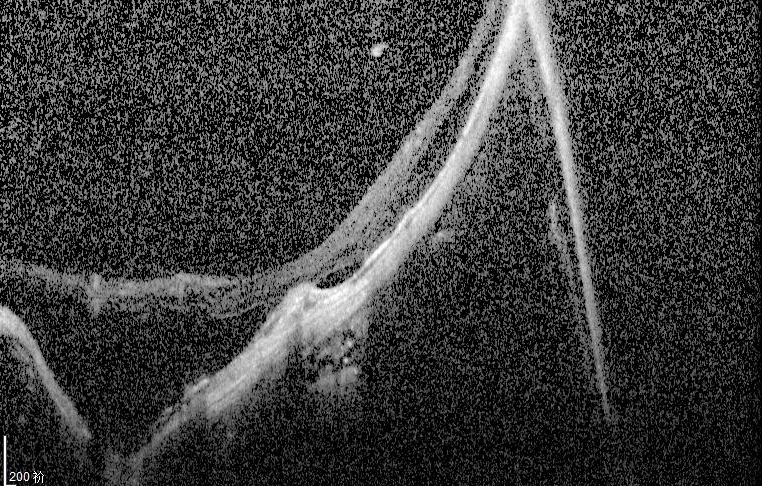

我检查以后发现他双眼的裸眼视力都非常差,右眼只有50公分数指,左眼只有0.02,矫正视力右眼戴2000度眼镜勉勉强强可以看0.05,左眼戴1900度眼镜也只能勉勉强强看到0.15,双眼晶状体轻度浑浊,玻璃体浑浊。最令我吃惊的是老人家双眼黄斑区视网膜不仅萎缩得像一张薄纸,而且还有劈裂性脱离及视网膜下陈旧性疤痕形成。

右眼手术以前眼底(萎缩、劈裂性脱离及视网膜下陈旧性疤痕)

左眼手术以前底(萎缩、劈裂性脱离及视网膜下陈旧性疤痕)